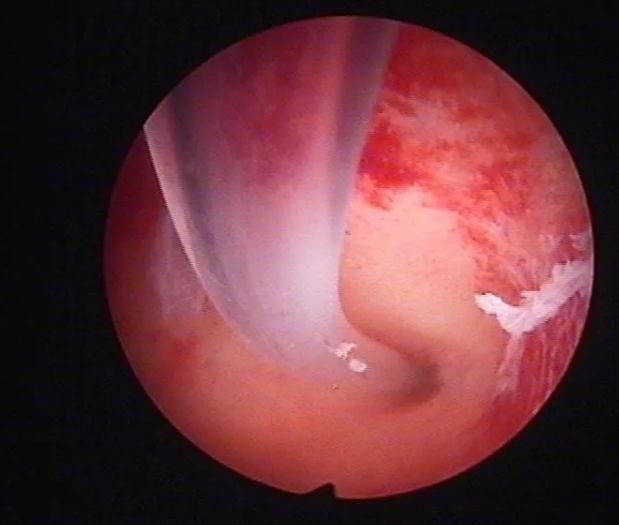

宫腔占位性病变:子宫内膜息肉、子宫肌瘤、子宫腺肌瘤、宫内异物(宫内节育器嵌顿、残留、剖宫产不吸收缝线)等均为宫腔内占位,会影响受精卵着床从而导致不孕症。通过宫腔镜可以准确定位病变位置,可以直接在宫腔镜下行子宫内膜息肉摘除术、异物取出术,对于较大病变及子宫肌瘤可住院行麻醉下的电切术治疗。

子宫内膜病变:当存在子宫内膜增生、慢性子宫内膜炎、宫腔粘连等异常情况时,受精卵无法着床,导致不孕。宫腔镜检查可以发现内膜的异常情况,进行相应的治疗。增生内膜可以通过刮宫术+药物治疗;子宫内膜炎需要抗炎治疗;轻度宫腔粘连可直接行器械钝性分离,重度宫腔粘连则需要住院治疗。

传统输卵管通液术时,通液管只插入宫腔,液体被注入宫腔后再进入输卵管,输卵管腔内获得的压力有限,如果有输卵管阻塞存在,加压疏通治疗效果差,只有在输卵管阻塞程度很轻时才有可能被疏通 宫腔镜下输卵管插管通液术时,将通液管直接插入输卵管开口,注射器能以比传统输卵管通液术大几倍甚至十几倍的压力直接将液体注入输卵管腔,可以使阻塞的输卵管腔内部分粘连和轻、中度阻塞得以分离、疏通,取得了较好的临床治疗效果。如果诊断为输卵管近端梗阻,则可以在宫腔镜下行导丝疏通术,疏通后使用防粘连药物避免再次粘连,临床治疗效果满意。